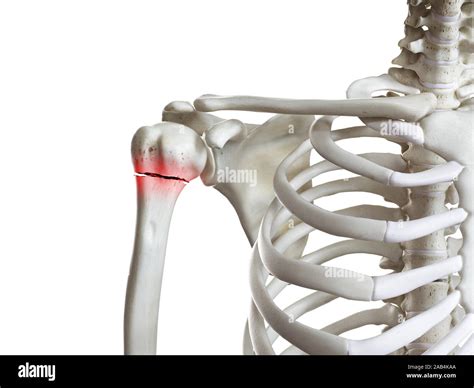

Proximal Humerus Fracture Occurs near the shoulder joint, often involving the head or neck of the humerus.

📝 Note: The type of fracture can influence the treatment approach and recovery time.